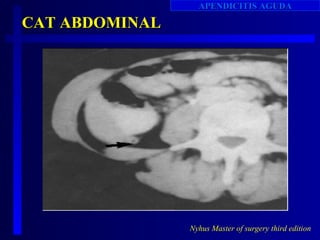

CAT ABDOMINAL

Nyhus Master of surgery third edition